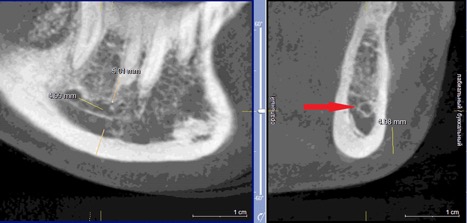

При измерении расстояния от резцовой петли до вестибулярной стенки нижней челюсти и её топографии в области правила «трёх пятёрок», выделено три положения канала, в котором проходит резцовая петля: канал прилежит, т.е. стенка канала образована кортикальной частью (рис 3), касается, т.е. имеет одну общую точку (рис 4) и не имеет общих точек.

Рисунок 3. КЛКТ Сагиттальный и коронарный реформаты переднего отдела нижней челюсти.

Стенка канала образована кортикальной частью кости.

Красная стрелка – «резцовая петля».

Красный пунктир – канал проходит в проекции участка правила «трёх пятёрок».